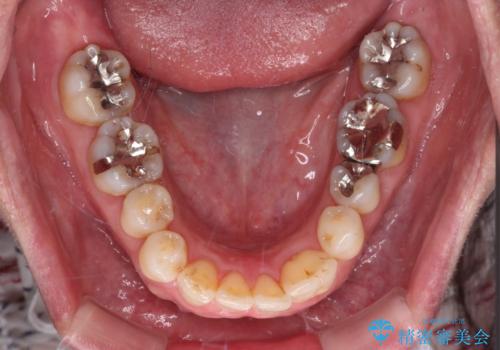

- 長年前歯の歯並びで悩んでいるとのことで来院された患者様です。

機能的なことを考えると八重歯となっている犬歯は抜歯せず、歯列を改善することが望ましいとされますが、数十年もの間犬歯がない咬み合わせで問題なく過ごしてきたため、八重歯を抜歯することで、手っ取り早く歯列を改善することとしました。